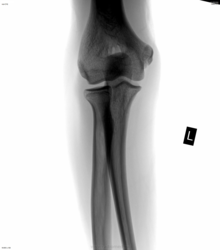

Парень, 14 лет. Не может разогнуть руку полностью (на 180*) в локте. Левую чуть больше, правую чуточку меньше. Как нужно (возможно, и правильно) описать эту вещь?

Так ведь на боковой линией уже обведено, что, по-моему, от мыщелков плечевой немного далеко...

Каюсь. Грешен. Решил, скиалогия за счёт минимального разворота. Для периостита широко, для кости - не так плотно. Для межмыщелковой сумки - самое то. Но не уверен, что есть там это оно...

теперь присматриваюсь ко всем локтевым суставам; сегодня был молодой человек 18 лет, так у него похожая тень была в этом месте, может это место прикркпления разгибателей так может выглядеть ?

Я тоже ещё этим сообщением не "отболела". Сегодня тщательно изучала на всех встречающихся локтевых суставах "зону интереса". Картина сходная. Так, может быть это норма, скиалогические эффекты?!